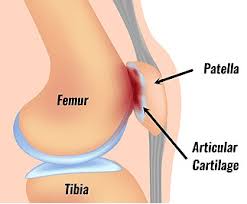

Patellofemoral Pain Syndrome (PFPS), commonly called Runner’s Knee, is one of the most frequent causes of front-of-knee pain. It occurs when the kneecap (patella) doesn’t glide properly in its groove on the femur (thighbone), leading to irritation of the surrounding structures.

These factors can all contribute to poor tracking of the patella, increasing pressure and pain.